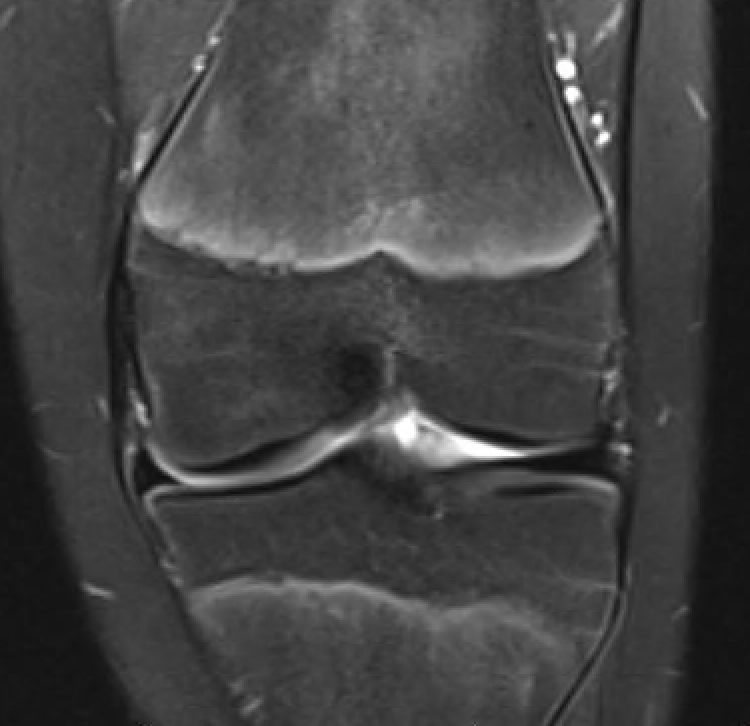

MFC OCD on presentation T2 image 6 months later

Stable lesion with no cysts Stable lesion with cysts